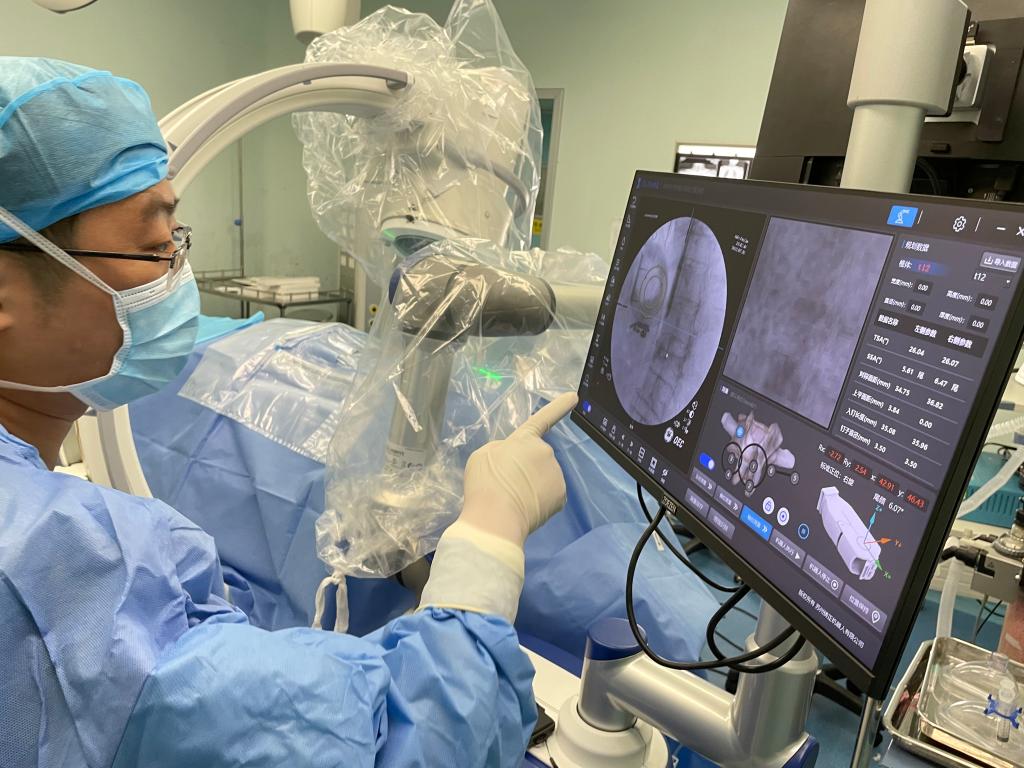

6月30日,骨关节外科成功为一例复杂椎体压缩性骨折病人在局麻下行机器人辅助经皮椎体球囊扩张成形术。在王坤正主任的指导下,宋金辉副主任医师、张晨副主任医师借助机器人术前规划与术中辅助,快速高效完成了该手术,患者取得满意疗效。

术前,王坤正主任团队采集患者的三维CT数据并将其导入到机器人术前规划系统中,机器人工程师与其配合确定穿刺位置、角度、深度等信息,制定出适合患者本人的个性化手术方案并在术中由机器人予以实施。

在该机器人辅助手术过程中,仅需通过正侧位进行伤椎识别,通过软件将正侧位透视图与术前规划数据的结合,即可得到病人伤椎的姿态以及实际的穿刺角度,之后机械臂根据软件参数进行精准定位,手术医生在机械臂引导下一次性进针成功,并对进针位置角度表示满意,整个过程少于20分钟,实现了手术的更精准化、高效化。相较于传统定位流程,术前规划只能保存在医生脑海中,术前与术中流程无法很好的衔接,术中穿刺依赖医生丰富的经验,对于情况复杂的病人,术中需要反复试验,导致手术时间延长、患者受辐射量增加。后续放置球囊、注入骨水泥等操作则同传统手工操作。